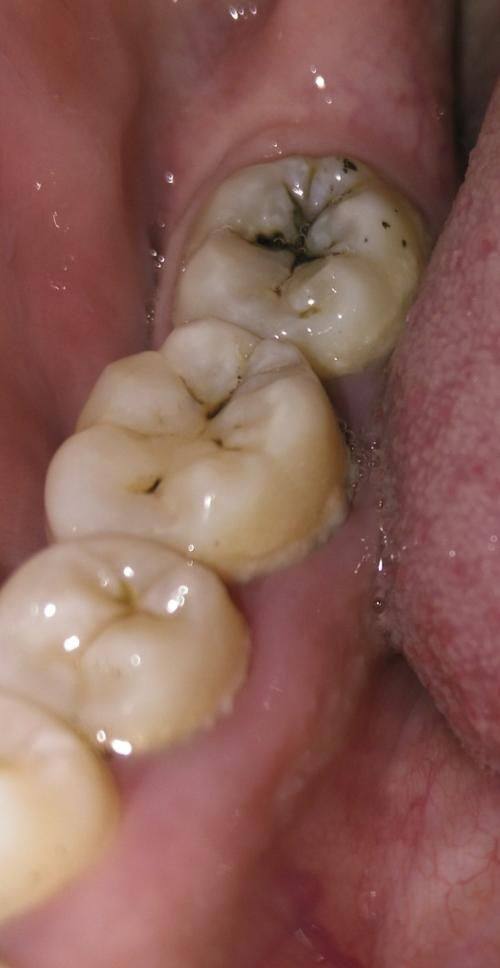

补牙:采用合规材料开展补牙修复,修复牙齿形态与功能

韩国江南人爱牙科补牙:300元起/颗